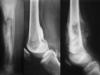

Локализация остеосаркомы

Остеосаркома

может возникать в любой

кости

скелета. Типичная локализация – метафизы

длинных

трубчатых костей с распространением на диафиз

до

закрытия ростковой зоны и на эпифиз после

синостоза метаэпифизарной области.

любит расти по поперечнику кости.

Более,

в половине наблюдени процесс

в

й коленного сустава

области

чем

бедренной

: кости,

проксимального

локализуется

–отдела

большеберцовой кости; далее

по дистального

частоте поражений следует проксимальный

отдел

плечевой кости, реже – малоберцовой кости и

бедренной кости.